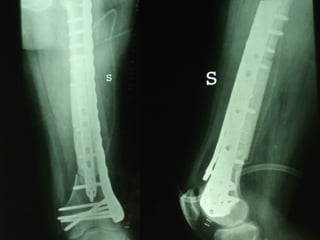

Dal Gennaio 2000 al Febbraio 2006 abbiamo trattato 167 fratture chiuse  con placca percutanea  in 164 pazienti :  27 lesioni diafisarie di gamba, 12 piloni tibiali ,  11 fratture prossimali di tibia, 36 fratture sovracondiloidee di femore, 17 fratture diafisarie di femore, 43 fratture metaepifisarie prossimali di omero, 21 diafisarie d’omero.  156 guarigioni 8 fallimenti

I buoni risultati ottenuti dipendono da 5 punti fondamentali:   una accurata riduzione percutanea della frattura  precise vie di accesso  l’utilizzo della placca che consenta il più lungo braccio di leva possibile il pretensionamento della placca  una sintesi con un ridotto numero di viti

Placche lunghe e pretensionate

Placche lunghe e pretensionate Sintesi con un ridotto numero di viti

Dal Gennaio 2000 al Dicembre 2005 27 placche LISS di femore